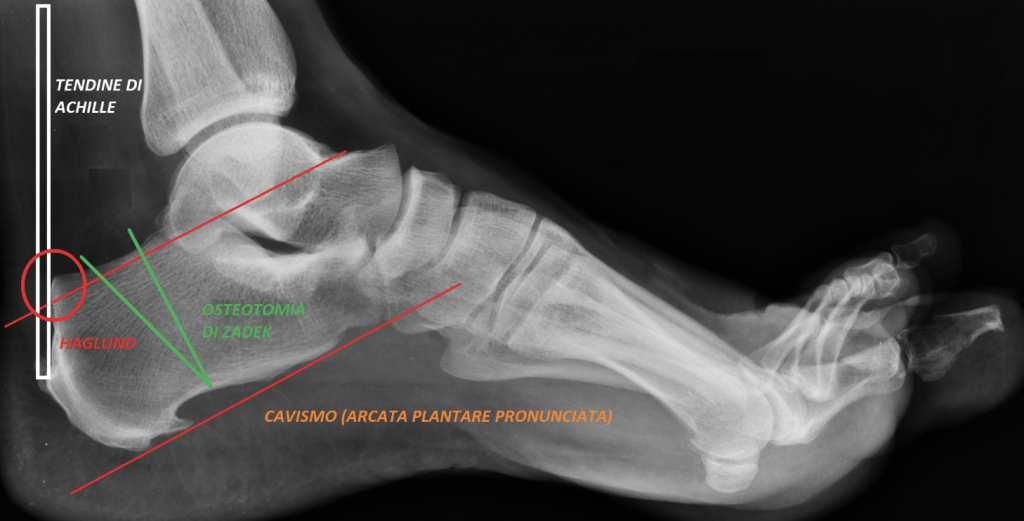

La malattia di Haglund, dal nome del chirurgo ortopedico svedese Patrick Haglund che la illustrò per primo nel 1927, consiste in un’alterazione della morfologia del calcagno che forma un prolungamento osseo verticale nella tuberosità postero-superiore a forma di sperone, che crea conflitto con il tendine di Achille. Tale situazione provoca ispessimento della borsa situata dietro il calcagno (borsite) con ispessimento delle fibre tendinee che si inseriscono in tale sede e gonfiore del pannicolo adiposo ivi situato. Imputato principale di tale fastidiosa e dolorosa patologia è il cavismo del piede (con pronunciato arco plantare) che spinge posteriormente il calcagno nel tendine stesso. Il metodo diagnostico più utilizzato è quello delle linee di passo parallele (come in figura) che si ottiene tracciando una linea tangente alla superficie inferiore del calcagno ed un’altra linea parallela ad essa nella sede del punto più alto sulla superficie posteriore dell’articolazione sottoastragalica. Se la tuberosità supera questa linea, la diagnosi è confermata. Le soluzioni chirurgiche, laddove ghiaccio, antiinfiammatori e riposo non siano risolutivi, sono date dall’asportazione chirurgica dello sperone, che può essere eseguita in modo mini-invasivo per via artroscopica con approccio posteriore (oppure tramite incisione chirurgica laterale), come nel caso del piede sinistro della campionessa olimpionica Vanessa Ferrari, che richiederà sei mesi di recupero, in considerazione della necessità di sottoporre ad intervento anche la caviglia destra per l’ asportazione di tessuto infiammatorio in sede articolare. Un’altra soluzione chirurgica interessante è data dall’osteotomia di Zadek, che consiste nell’asportazione di un cuneo osseo dal calcagno (che viene successivamente stabilizzato con viti o cambre) ad anteriorizzare il calcagno al fine risolvere definitivamente il conflitto tra sperone e tendine di Achille.

Malattia di Haglund repertata in un piede. Si notano le linee di passo parallele (diagnostiche) ed il conflitto con il tendine di Achille.